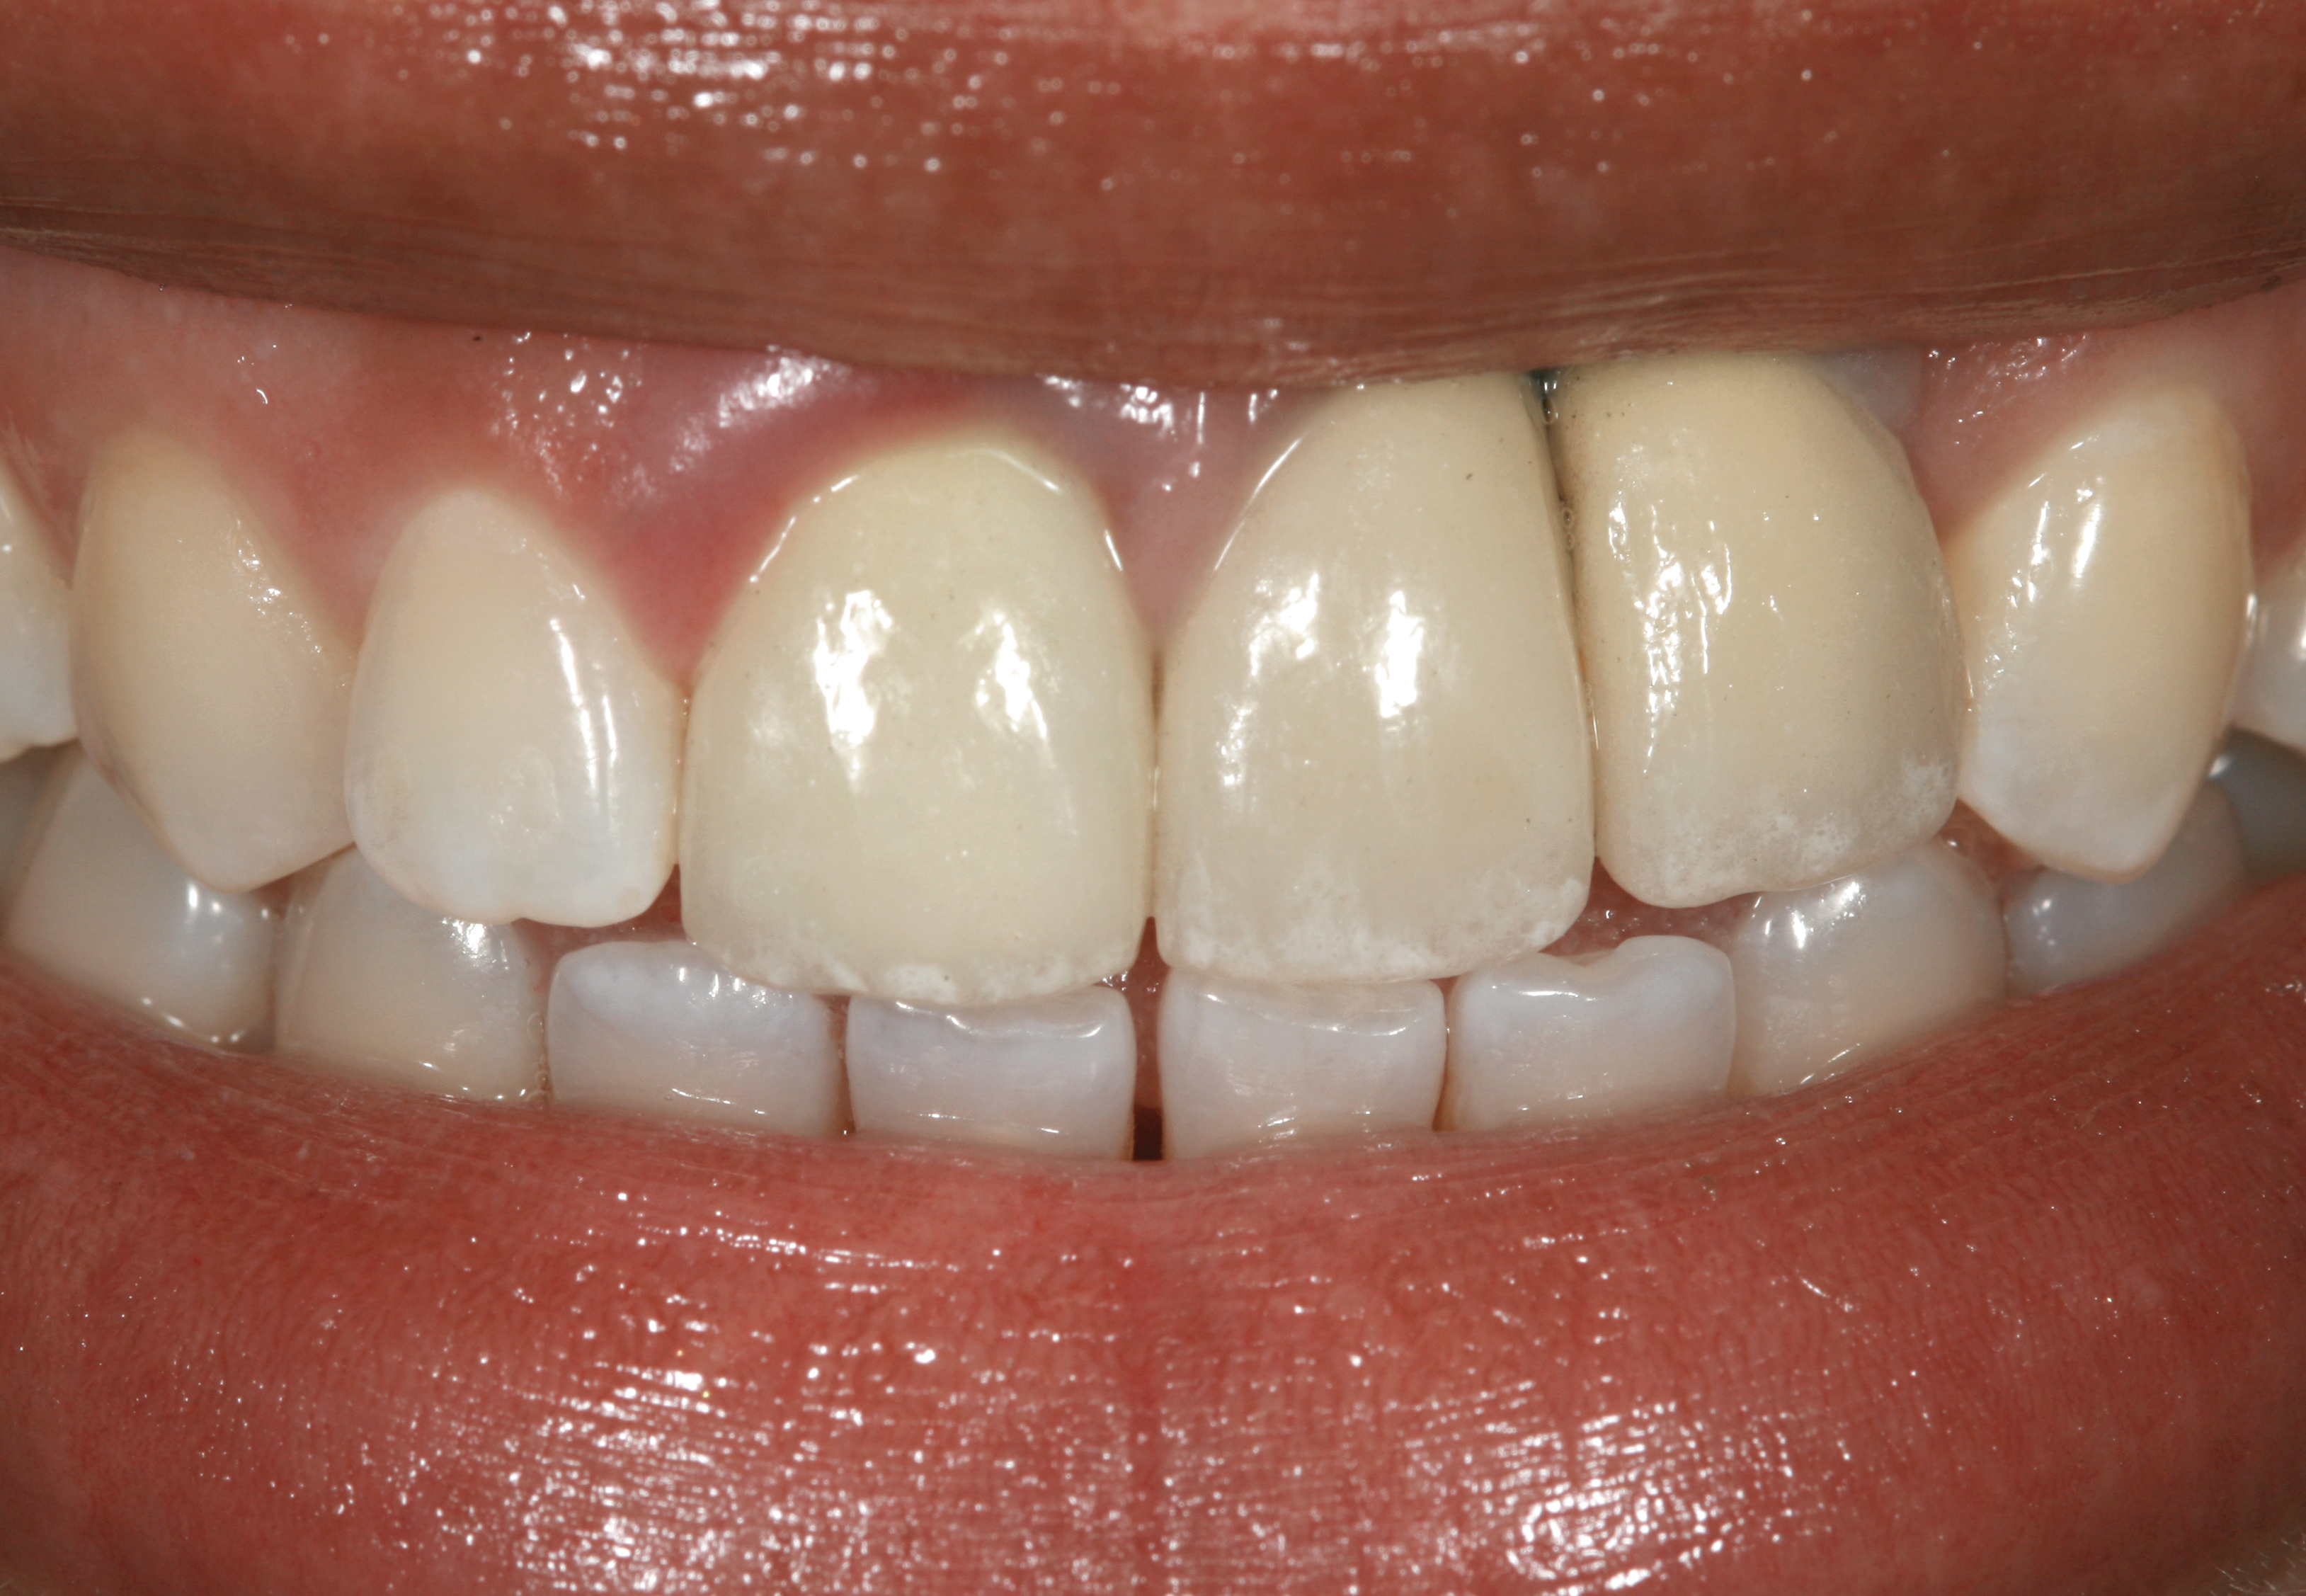

Problem: Two adjacent implants are located in the central–lateral incisor positions, and the patient has a high smile line along with loss of inter-implant papilla and midfacial recession around both implants (Figure 29 and Figure 30).33-38

Solution: Decoronate the implants by placing cover screws over both of them. Two weeks later, place connective tissue grafts and/or dermis allograft over the cover screws to augment soft-tissue volume. Repeat the mucosal grafting procedure as needed. Expose one of the implants in a more favorable prosthodontic position, and then create an ovate pontic over the submerged implant with a cantilevered fixed dental prosthesis design (Figure 31).

Fig 29. Two adjacent implants placed in the esthetic zone can lead to loss of the interdental papilla and a negative outcome for a patient with a high smile line.

Fig 30. The intraoral view of the loss of the interdental papilla between teeth Nos. 9 and 10.

Fig 31. The solution to the problem in Figure 29 and Figure 30 was to decoronate the implants, augment the site, uncover 1 implant, and place a cantilevered cement-retained 2-unit implant-supported fixed dental prosthesis.